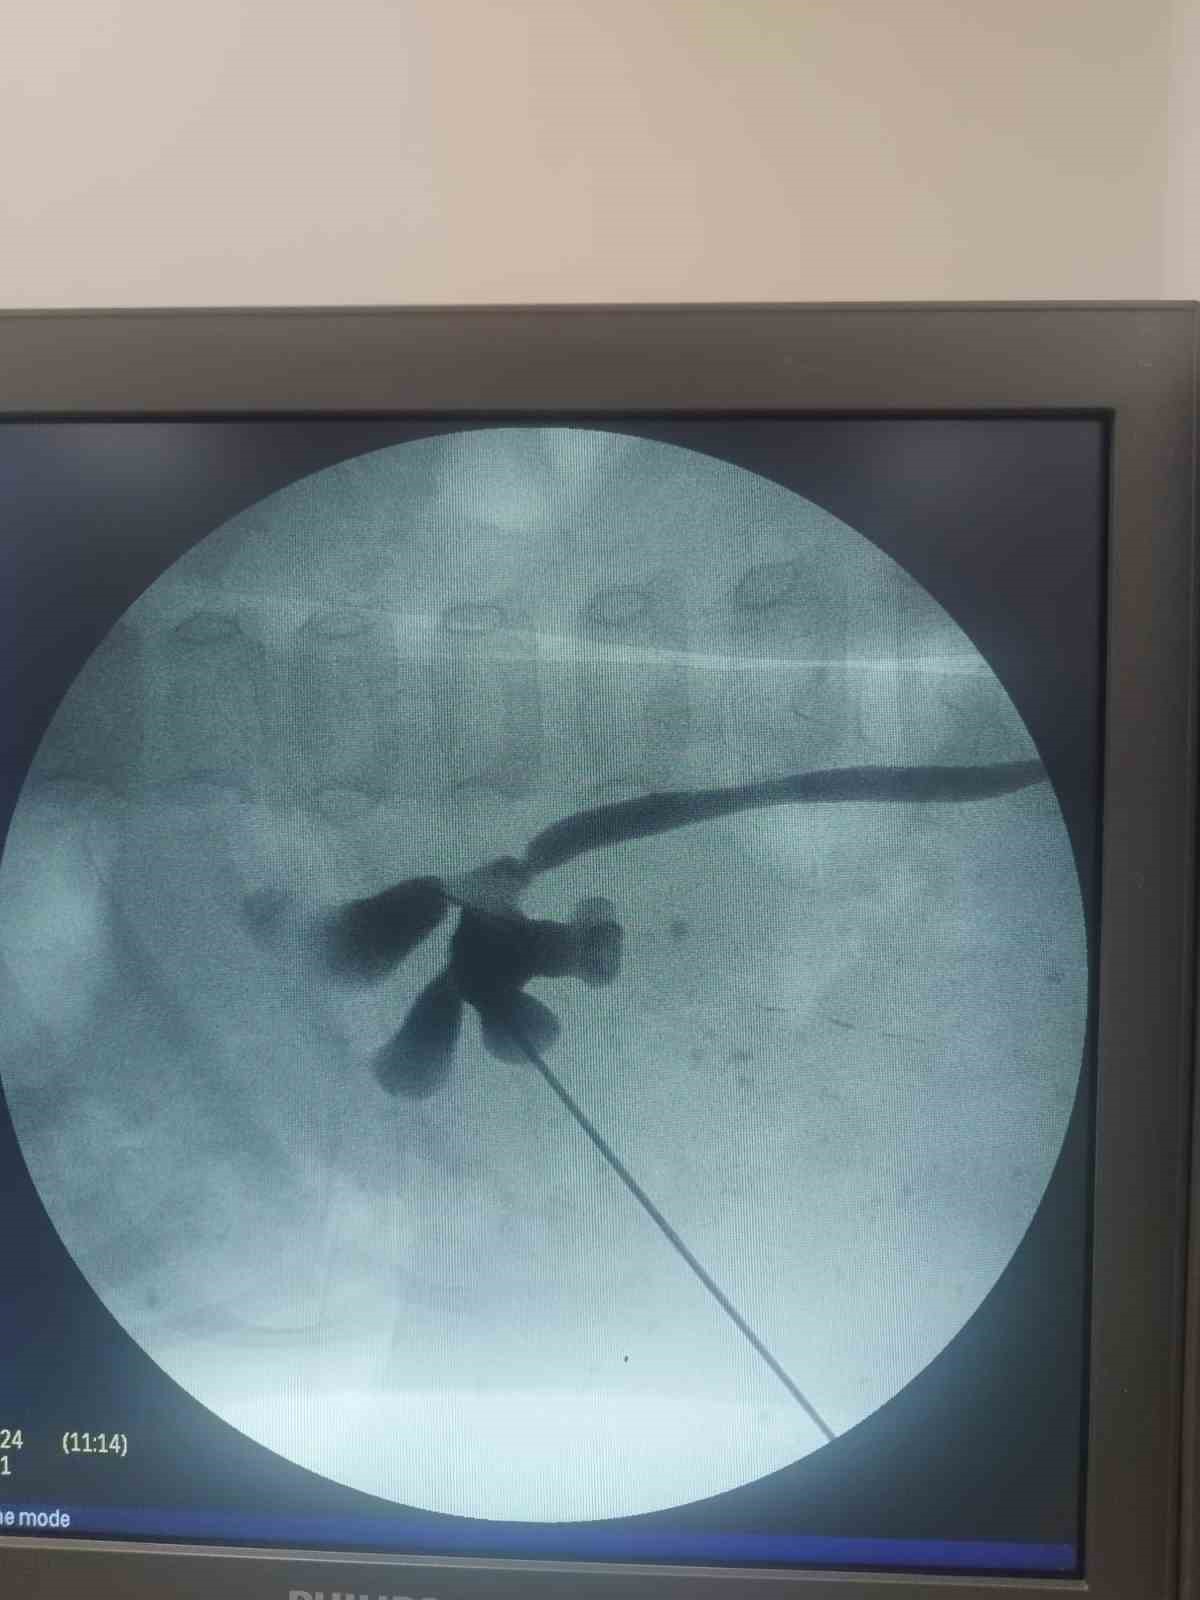

Hastanın yaşı nedeniyle oldukça özel bir operasyon gerçekleştirildiğini belirten Üroloji Kliniği eğitim sorumlusu Doç. Dr. Kadir Yıldırım, "24 aylık bebeğimiz Zeynep’in kapalı böbrek taşı ameliyatını başarıyla gerçekleştirdik. Yavrumuzun böbreğinde 1.5 santimlik bir taş vardı. Süper mini ya da ultra mini PNL diye adlandırdığımız özel aletler kullandık. Bebeğimizin durumu şu an gayet iyi" dedi.